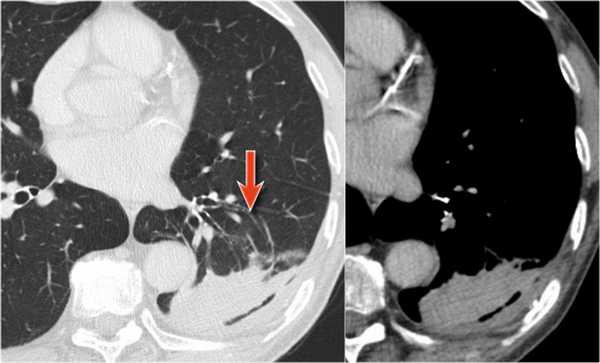

На КТ снимках синей стрелкой указан долевой ателектаз, а красной стрелкой опухоль, которая обтурирует левый верхний долевой бронх (центральный рак легкого.

Ателектаз верхней доли левого легкого с типичным симптомом воздушного серпа (Luftsichel sign — luft(air)+sichel(sickle)), обусловленный гипервентиляцией верхнего сегмента нижней доли левого легкого на фоне коллапса верхний доли левого легкого. Гипервентилируемый

сегмент визуализируется на прямой рентгенограмме от дуги аорты до апикальной части легкого.